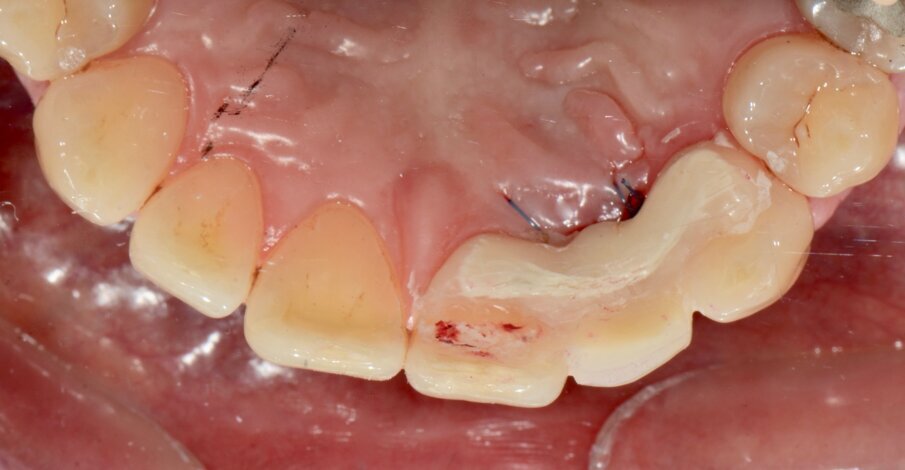

Fig. 17: Intra-oral view after removal of the horizontally fractured tooth #21.

The socket shield technique was planned for this case. Vertical root sectioning was done, removing the palatal part of the root and leaving the facial section intact. Another CBCT scan was taken, and it showed the guide pin in place (Fig. 19). The implant was placed without flap elevation (Fig. 20), and bone substitute was placed to fill the gap (Fig. 21). A screw-retained provisional restoration was placed immediately after implant placement to guide the periodontal tissue healing (Fig. 23). Four months after the procedure, the definitive screw-retained restoration was placed, and very satisfying aesthetic and functional results were evident (Fig. 24).

A 39-year-old male patient presented to our clinic with a fractured tooth #21 (Figs. 16 & 17). The CBCT scan showed an unfavourable root–crown ratio for tooth #21 (Fig. 18), which was an indication for extraction.